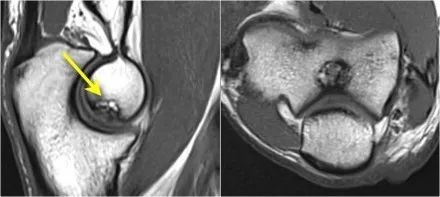

肱骨小头OC病变

慢性过度外翻可导致肘外侧的骨软骨病变。这是重复冲击和剪切力的结果。

下面的射线照片是一名15岁的棒球运动员,有4年的肘部疼痛史以及最近一次锁定。肱骨小头有一个局部透明度区和一些破碎,这是典型的小头骨软骨病变,

这对于头状骨的是典型的,锁定可能是游离体的结果。

MR-关节造影证实了骨软骨病变。在肱骨和骨软骨病变之间存在钆造影剂,这表明它是不稳定的。注意轴向图像上看到的碎片。